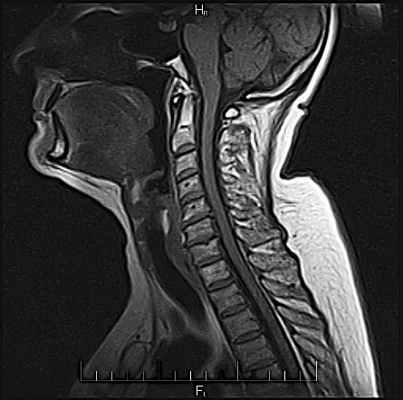

Небольшого размера грыжа шейного отдела позвоночника:

Такого размера грыжи могут протекать бессимптомно.

На МРТ снимке, который ниже, видны не только нижнешейный отдел позвоночника, но и грудной. Удачное сочетание, поскольку шейно-грудной переход нередко бывает причиной боли: